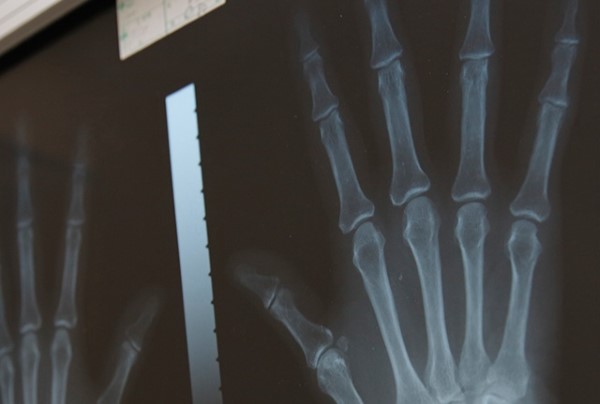

東京都豊島区池袋に位置する整形外科クリニックで、池袋駅から徒歩圏内にアクセスしやすく、整形外科専門医が交通事故によるむち打ち症や骨折、打撲に対してレントゲンや超音波検査で症状を詳しく診断します。リハビリテーションと連携しながら、早期の社会復帰を目指します。

レントゲン画像を指差しで丁寧に説明してくれて、こちらからの質問にもわかりやすく答えてもらえました。リハビリも継続して通ったところ、痛みが徐々に和らいできました。

首の痛みで来院しました。レントゲンを撮ってもらい、画像を見ながら異常の有無や神経への影響までわかりやすく説明していただけました。